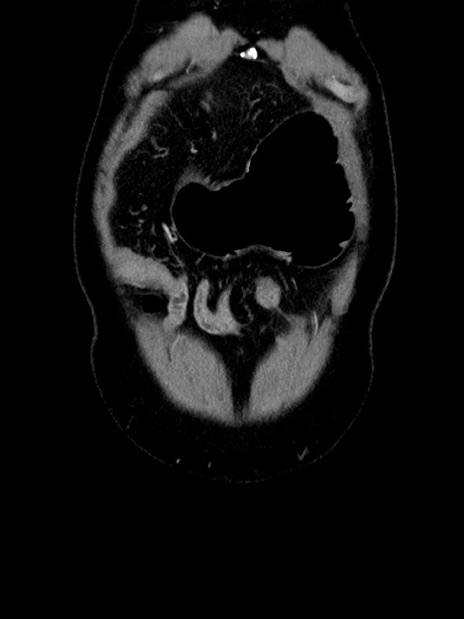

症例35(冠状断像)

【症例】70歳代 男性

【主訴】腹部膨満、嘔吐

【現病歴】昨日より腹部膨満感出現。本日増悪し、仙痛出現。嘔吐あり、受診。

【既往歴】糖尿病、胆摘後

【身体所見】BP 149/80mmHg、HR 74/min、BT 35.9℃、腹部:膨満、軟、圧痛なし。腸雑音減弱あり。上腹部正中切開瘢痕あり。

【データ】WBC 13500、CRP 1.72